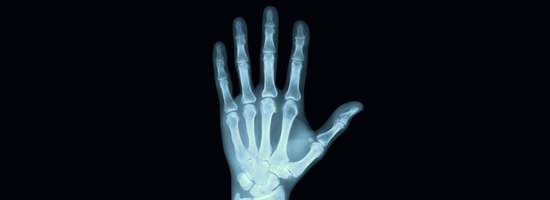

Hand and Arm Pain

Arm and Hand

Your hands and arms play an essential role in everything you do—from gripping a coffee mug to lifting your child. When pain, stiffness, or injury interferes with your daily life, you need care you can trust.

Our orthopedic specialists are highly trained in diagnosing and treating a wide range of hand and arm conditions. Whether you're dealing with a sudden injury or a chronic issue, we're here to restore function, relieve pain, and help you get back to the activities you love.